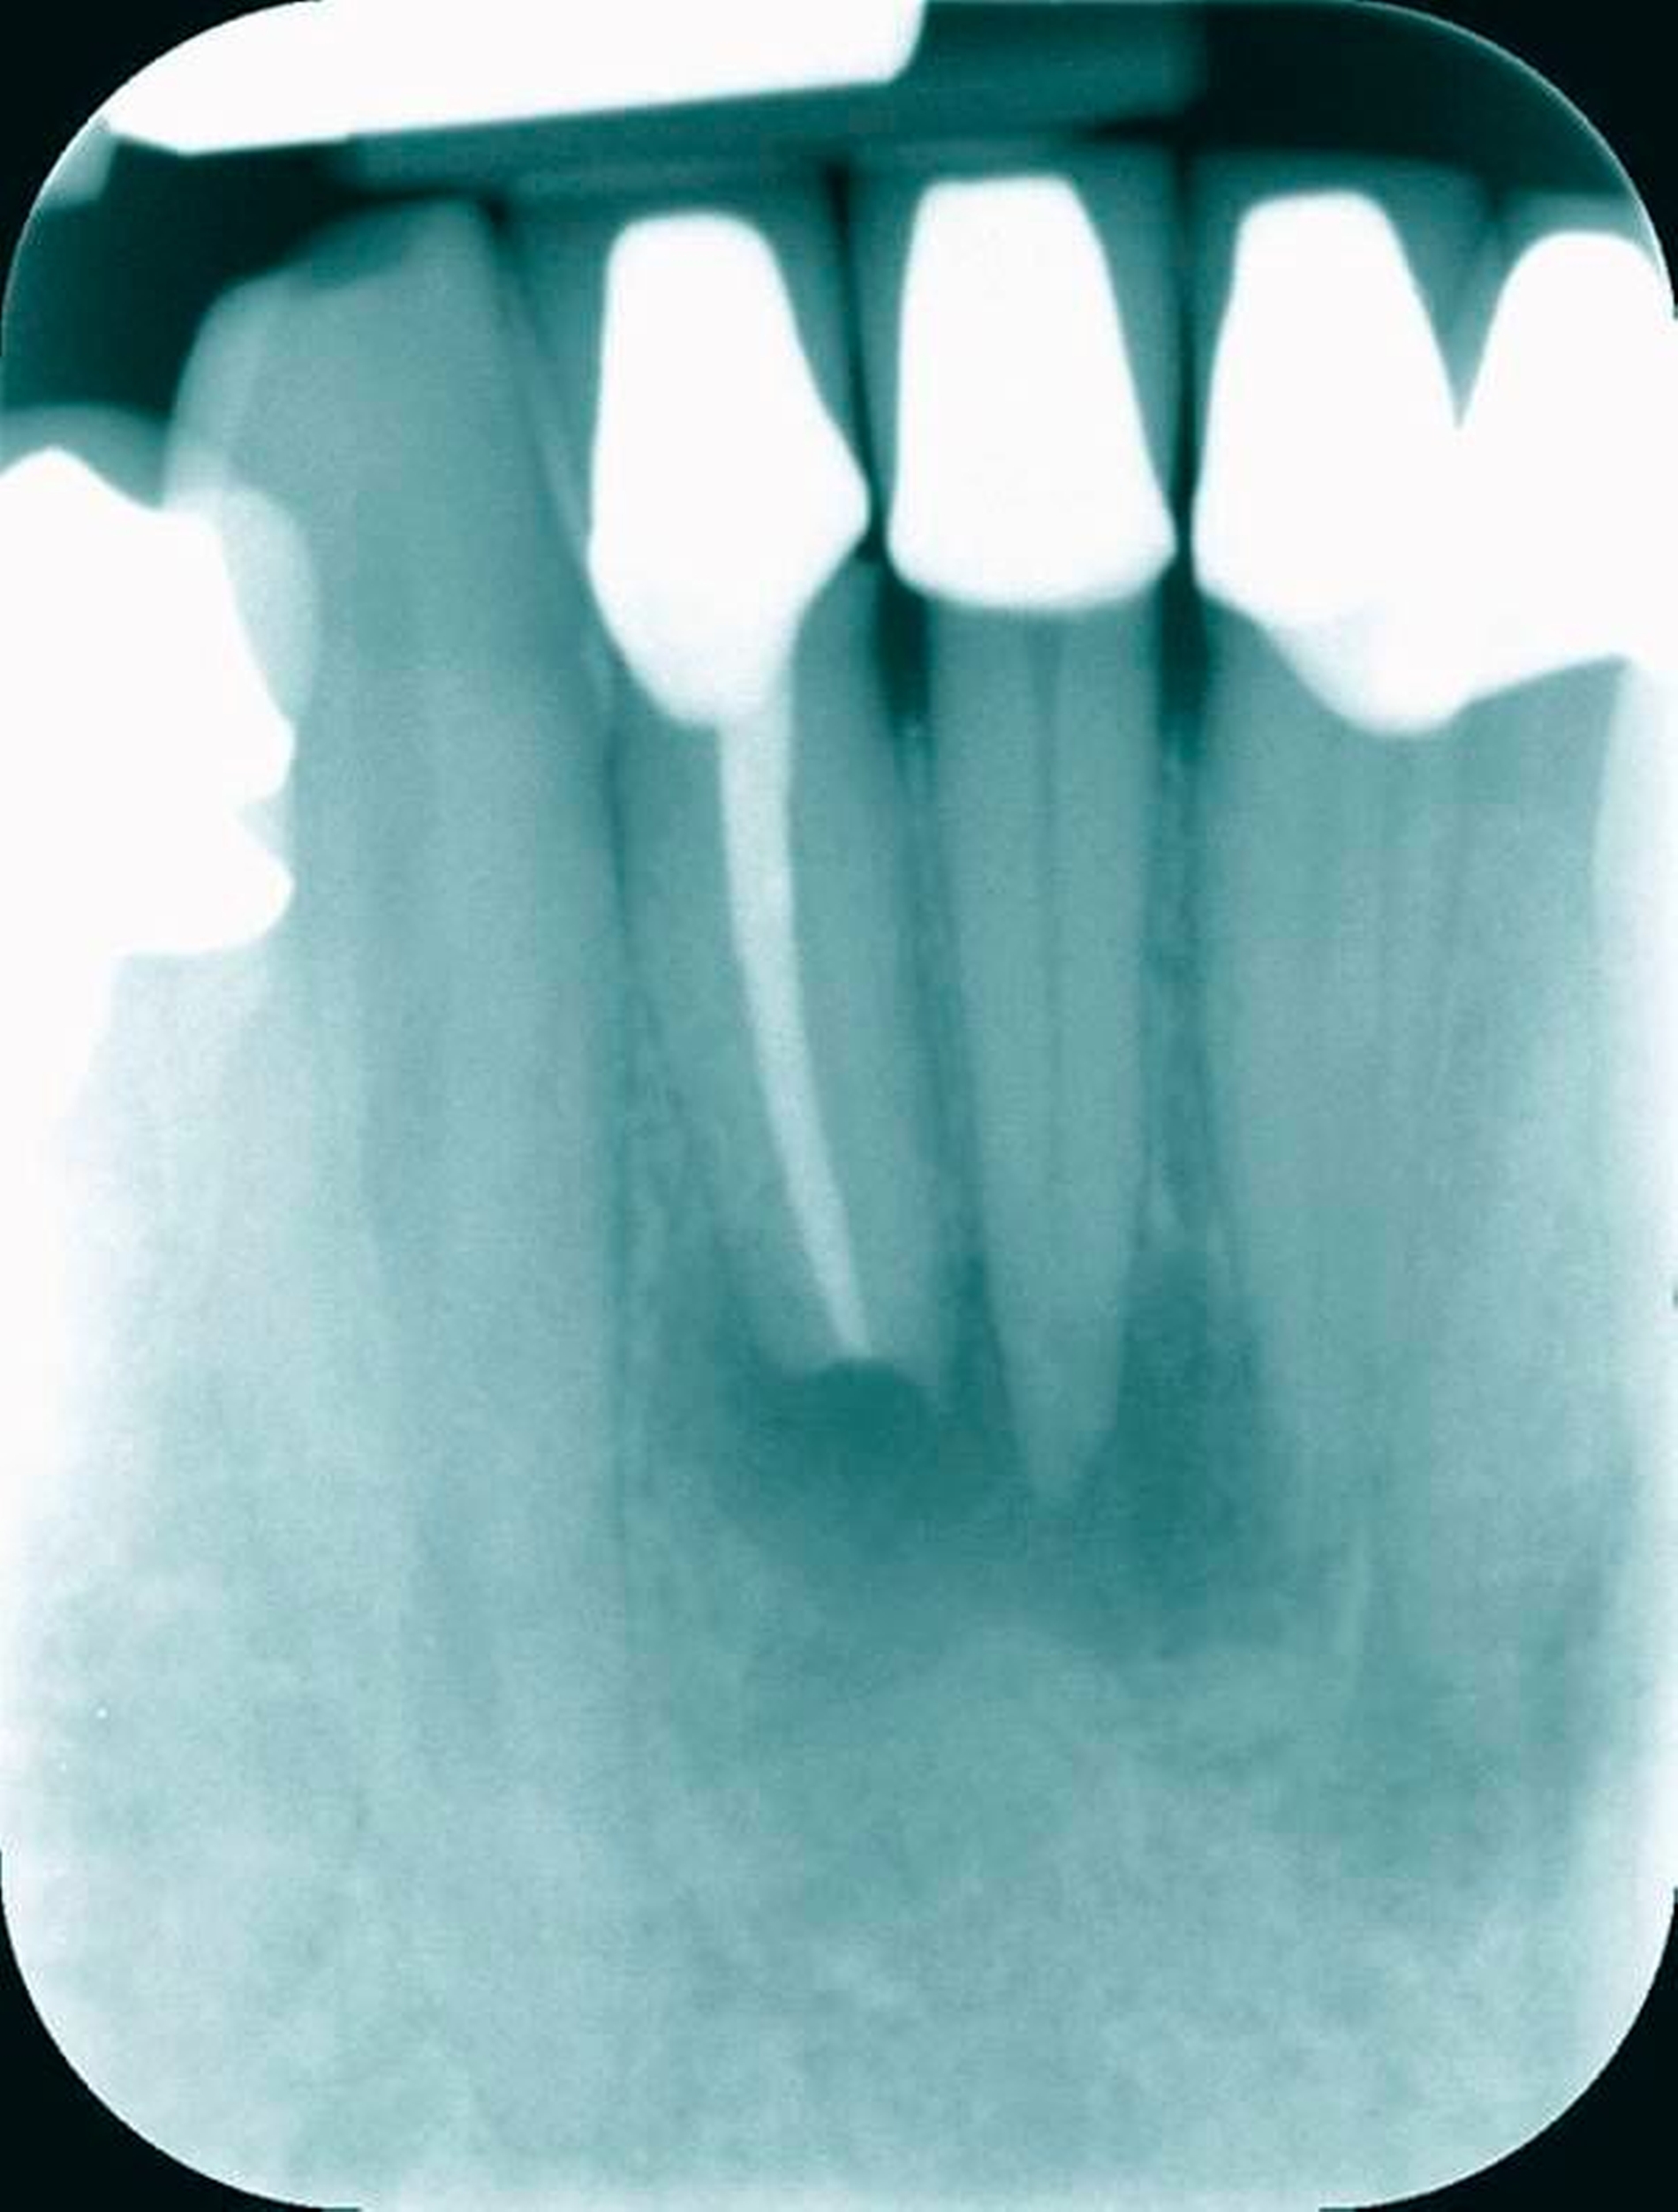

Häufig ist zu beobachten, dass die lateralen Schneidezähne sowohl in der Wurzellänge als auch in der Breite größer sind als die zentralen und entlang der Wurzelfläche auf der mesialen und der distalen Seite eine Einziehung unterschiedlicher Tiefe aufweisen [Hollaender, 1870; Schumacher, 1985]. Je ausgeprägter diese ausgebildet ist, desto sicherer liegt innerhalb der Wurzel eine Aufteilung der Wurzelkanäle vor. Das Verhältnis von Länge und Breite der Zahnkrone kann als ein Hinweis auf ein mehrkanaliges Wurzelkanalsystem genutzt werden. Demnach lagen bei zunehmender bukko-labialer Ausdehnung der Zahnkrone in 70 Prozent der Fälle zwei Wurzelkanäle vor [Warren&Laws, 1981]. Im Einzelfall können bis zu drei Wurzelkanäle vorkommen. Im Rahmen der röntgenologischen Diagnostik kann eine Kontinuitätsunterbrechung des Wurzelkanalverlaufs als ein sicherer Hinweis auf eine Aufteilung der Wurzelkanäle gewertet werden (Abbildungen 9a bis 9c).

Nach einer eigenen Untersuchung von 400 unteren Schneidezähnen lässt sich die Aufteilung der Wurzelkanäle erst 3 mm unterhalb der Schmelz-Zement-Grenze ermitteln (Abbildungen 10 und 11).